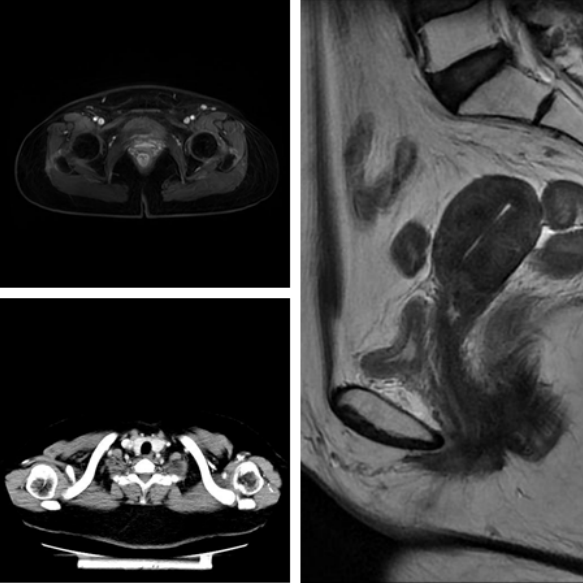

全身PET/CT检查显示(详见图片)卢女士宫颈软组织增厚高代谢,考虑宫颈癌;双颈、双侧锁骨区、右侧内乳、纵膈、左肺门、膈上、腹腔、腹膜后、双侧盆腔及双侧腹股沟多发肿大淋巴结,高代谢,考虑肿瘤转移;同时肿瘤标志物也高得惊人:SCC 346.2ng/ml,CA125 1863U/ml,CA199 253.3U/ml,CEA 104.1ng/ml。治疗团队又给卢女士行左锁骨上淋巴结穿刺病理,明确了转移性鳞癌,而宫颈活检病理则倾向腺鳞癌。

3周期治疗后,卢女士复查影像提示肿瘤缩小了51.2%;8周期化疗及靶向治疗,以及9个周期免疫治疗并联合调强放射治疗后,情况改善更为明显,患者无再出现阴道出血,肿瘤标志物降至正常水平,全腹MRI、颈胸部CT提示肿瘤病灶100%消退,疗效评估:完全缓解(CR)。

图片1:全身PET/CT:双颈、双侧锁骨区、右侧内乳、纵膈、左肺门、膈上多发肿大淋巴结,高代谢,考虑肿瘤转移。

图片2:全身PET/CT:1.宫颈软组织增厚,高代谢,考虑宫颈癌(2.8CM×2.3CM×5.0CM);2.腹腔、腹膜后、双侧盆腔及双侧腹股沟多发肿大淋巴结,高代谢,考虑肿瘤转移。

图片3.:治疗后复查腹部MRI:1.原宫颈病灶基本消退,现显示不清;2.腹股沟淋巴结未见肿大。肺部CT:双肺少许纤维灶,双侧锁骨区、右侧内乳区、膈上淋巴结短径小于0.5cm。